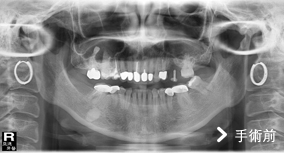

我們知道,一顆牙齒要屹立不搖,四周要有足夠的齒槽骨去支撐它;同理,「人工植體」也需要足夠的齒槽骨才能在植入後有良好的穩定度。

患者左上第一大臼齒缺牙,齒槽骨高度只剩下3公釐高度,但植牙需要至少10公釐高度的齒槽骨才能建造穩固的植體。

這種狀況下,可依患者狀況評估以「上顎竇增高術」,利用手術器械將「上顎竇膜」分離並提高,並填入骨粉,增加骨頭高度。因為竇膜易破,如傷到破損可能造成的併發症包括:上顎竇膜破裂、鼻竇炎、口腔與鼻竇相通、骨粉或植體感染,因此「上顎竇增高術」屬於較複雜的手術技巧,建議選擇臨床經驗豐富的醫師來操作較為適當。

手術後照片可以明顯看出齒槽骨高度已經增加,確定有足夠骨頭再植入一個植體,也順利替患者解決缺牙所帶來的不便。